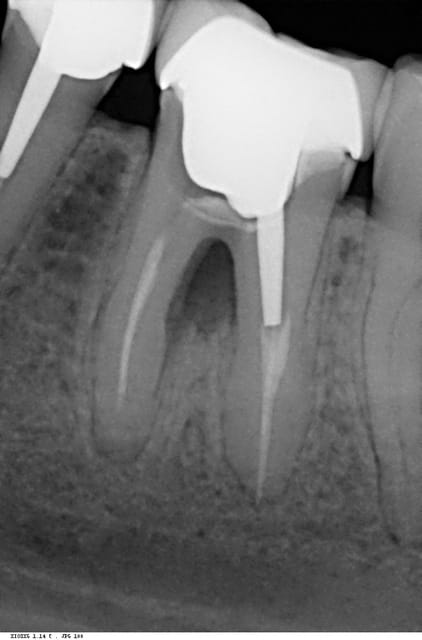

J'ai reçu ce jour une patiente de 21 ans pour une douleur sous une 36, couronnée.

A l'examen clinique j'ai une douleur a la percussion ainsi qu'un début d’abcès en lingual.

c'est pas une fracture de tenon, mais du a l'ag a mon avis

Ca ressemble pas à de l'amalgame.

On dirait une pièce coulée, mais dans ce cas, pourquoi le tenon n'est pas du même métal?

En tout cas le plancher est perforé, cassé ou carié, sûr de sûr...

Donc la dent est fichue.

Le tenon n'a pas la même radio-opacité que le reste car moins épais. Par contre pour l'adaptation de l'IC dans la chambre pulpaire il peut revoir sa technique d'empreinte. Sans parler de l'adaptation cervicale. Si tu compares avec la 35, c'est cohérent. Cohérent aussi avec l'aspect du matériau d'obturation qui ne ressemble pas trop à ce qu'on obtient avec de la gutta.

perfo du plancher visible à la radio. extraction et implant à 3 mois

l'os au niveau de la furcation est radioclaire ce qui est suspect...une palpation dans cette zone plutôt qu'au niveau du périapex devrait signer le diagnostic...

8 réponses pour quelque chose de facile à analyser sur la rétro, merci quentin...

Perfo plancher par reprise de carie, essai de sauvetage par un fond de cavité, un matériau radio opaque en tout cas, quid du collage ?... Mais ça n'a pas suffi.

Inlay-core pas trop bien adapté, en cause, la prépa et l'emp donc le prat, le proto ?

Essai de mise en place d'un ancrage radiculaire dans la racine mésiale. puis retour en arrière car perfo ou ?

Ça parait "circonscrit, cette perfo, donc sans doute, sans signe clinique...

Possible fissure de la racine mésiale sans doute en vestibulaire... ou en lingual, ou les 2, mais c'est pas fracturé, le ligament a l'air en bonne santé, signe clinique gingivale parfois évident, poche, etc...

Et sans doute la cause de la douleur à la percu.

Mais nous n'avons qu'une radio et un pano, alors...

En tout cas, pas de palabre, c'est mort, implant à 3 mois !